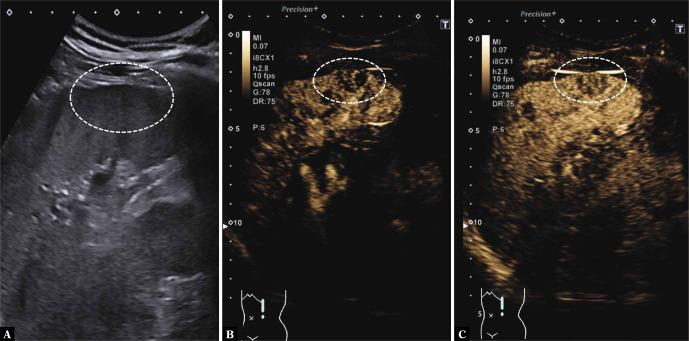

The aim of this case report is to present real-time CEUS-guided biopsy for diagnosing rare benign splenic pathologies after inconclusive findings on cross-sectional imaging. We present the case of a 50-year-old male patient who received a contrast-enhanced computed tomography scan of the thorax during the evaluation for lung transplant due to lung fibrosis, with incidental finding of disseminated hypodense splenic lesions. During follow-up imaging, the patient did not tolerate a complete MRI examination, and two acquired pulse sequences did not confirm the final diagnosis. While CT-guided biopsy revealed no results, CEUS-guided target biopsy with repeated contrast injections showed a benign littoral cell angioma of the spleen. The use of real-time CEUS-guided target biopsy during lesion washout may be a useful tool to improve the accuracy of biopsy and accelerate the diagnosis in patients with parenchymal lesions after inconclusive cross-sectional imaging findings which may pose a challenge for CT-guided biopsy.

本病例报告的目的是介绍在横断面成像检查结果不明确后,采用实时超声造影引导下活检诊断罕见的脾脏良性病变。我们报告一例50岁男性患者,因肺纤维化接受肺移植评估时,进行了胸部对比增强计算机断层扫描,偶然发现脾脏弥漫性低密度病变。在后续成像检查中,患者无法耐受完整的MRI检查,且两次采集的脉冲序列均未确诊。CT引导下活检未得出结果,而超声造影引导下的靶向活检经多次注射造影剂后显示为脾脏良性 littoral 细胞血管瘤。在病变消退期使用实时超声造影引导下的靶向活检,对于提高活检准确性以及加速诊断可能是一种有用的工具,适用于横断面成像结果不明确、给CT引导下活检带来挑战的实质器官病变患者。